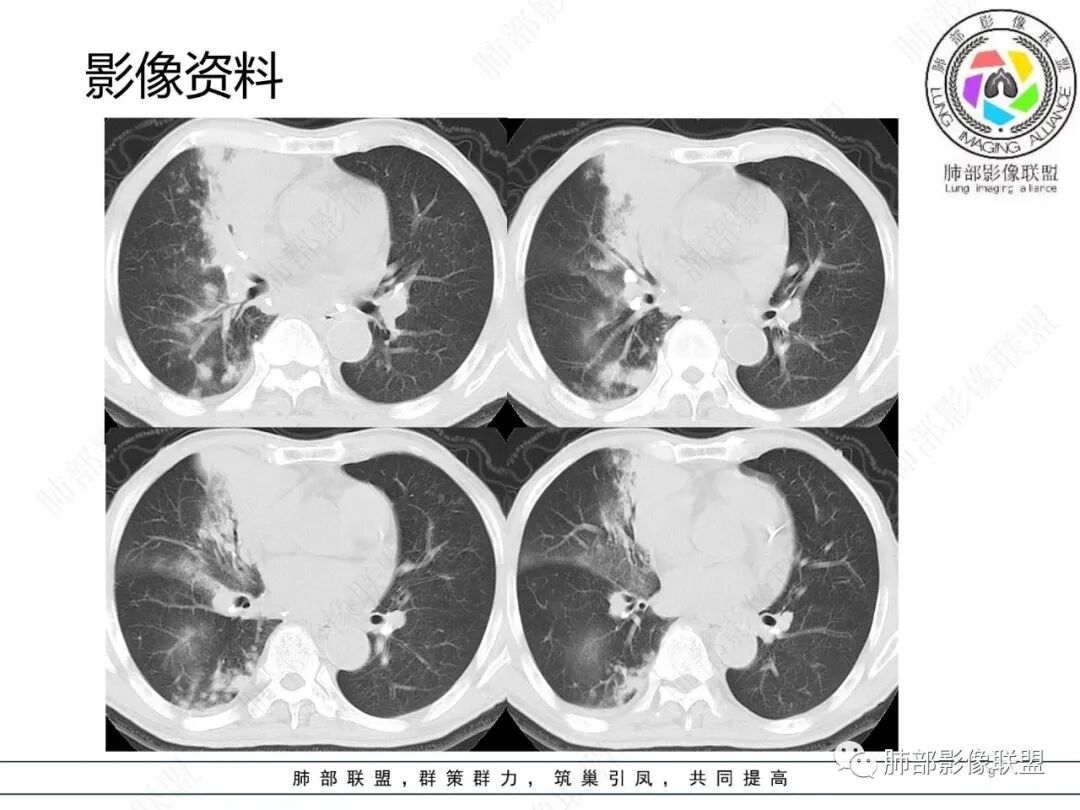

影像资料

2.胸部CT: 右肺病灶,主要累及右肺上叶前段、右肺中叶内侧段及右肺下叶背段,片状影及结节影,实性密度为主,部分磨玻璃晕,密度不均,散在钙化,其中上叶前段支气管闭塞,隐约见钙化突入。未见明确“硬树芽”或“拐枣征”。主要呈延迟强化,其间低密度区疑坏死或粘液成分。纵隔内见多组淋巴结肿大环形强化,部分钙化。

3.综合分析:影像病灶集聚(右肺上叶前段、右肺中叶内侧段),实性密度为主,钙化及液性密度区,淋巴结环形强化等,较常见于继发性肺结核,或伴其他混合感染(支气管阻塞)。尽管未见典型硬树芽。